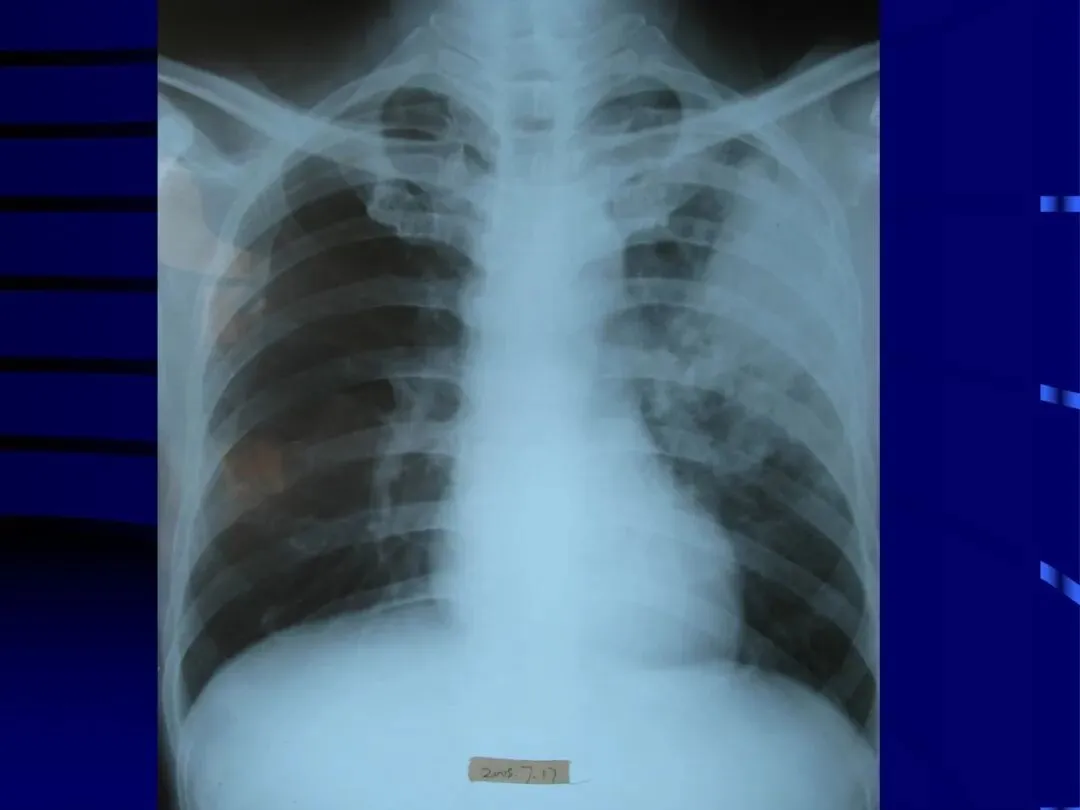

>内科学课件_肺部感染性疾病

内科学课件_肺部感染性疾病